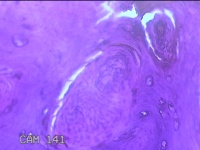

右侧拇指皮下结节

性别

男

年龄

40岁

临床诊断

皮下结节

一般病史

发现右侧拇指皮下结节1年余,无明显疼痛及不适。

标本名称

大体所见

灰白暗红色带皮肤结节0.8x0.3x0.2cm一个,表面糜烂,切开结节呈实性,切面灰白粉红色,质中。

图3